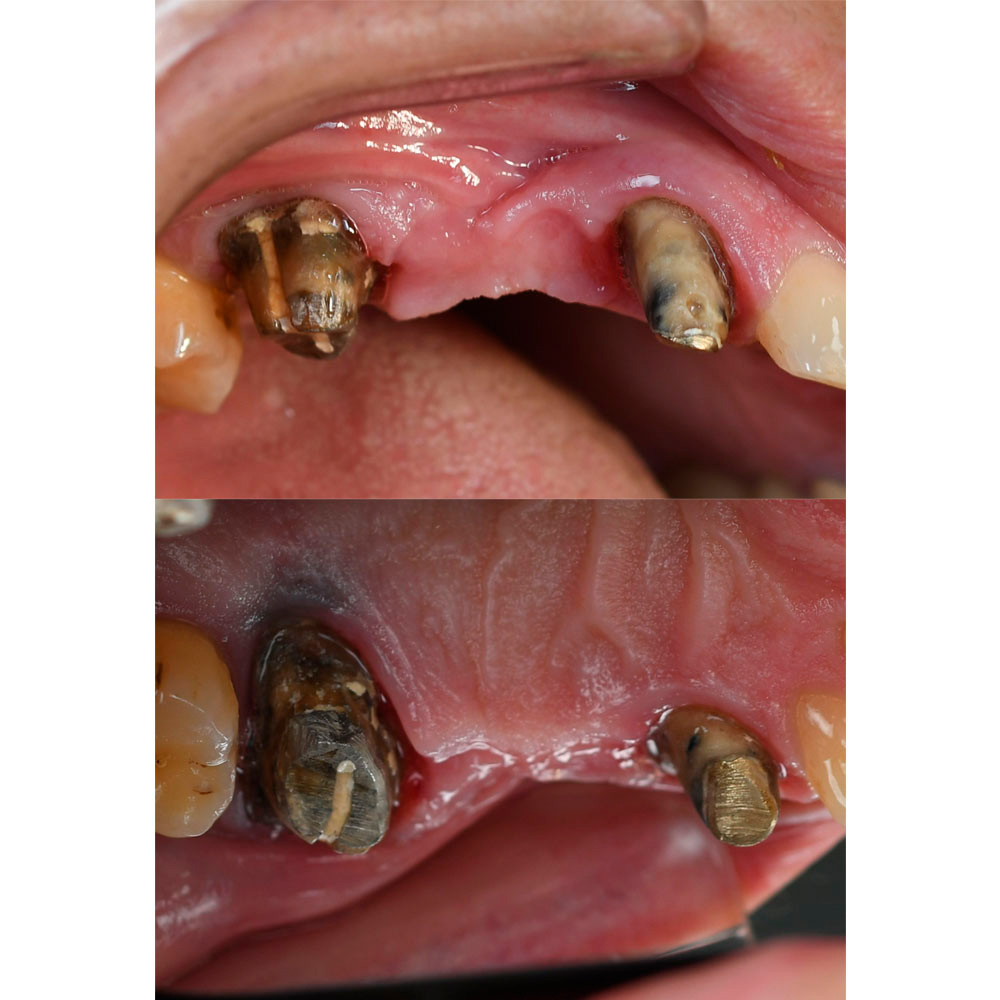

Dear colleagues, I would like to share a clinical case that I have been observing since 2017. A patient came to the clinic with complaints of swelling and pain in the area 1.3, 1.4, 1.5. Conservative therapy was suggested, and after dealing with the acute period, a surgical procedure including cleaning of the periodontal pocket, scaling and root planing and filling the bone pocket with DSI Syntoss Plus that contains beta-tricalcium phosphate granules. The procedure was performed in 2017, the old bridge was replaced with a new one, which is fixed with temporary cement for regular revision due to the unstable condition of 2.6. The patient is unable to undergo implantation for a number of reasons, so the 2.6 will be kept until the last possible moment. Its mobility is grade 2 and the condition of the mucosa can be seen in the photo. The whole process of bone maturation is shown on the x-rays. Thank you for your attention.